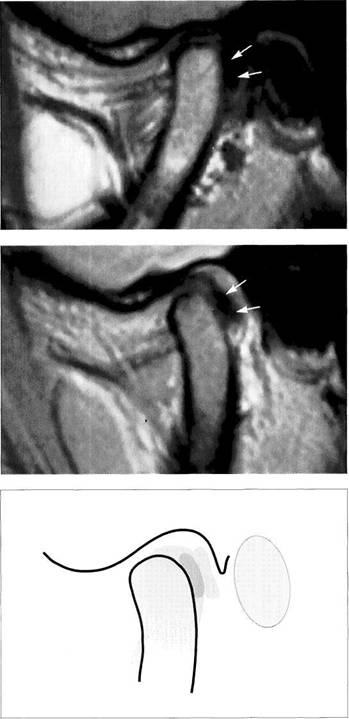

Disk Position in the Frontal Plane

The lateral and medial portions of the joint are evaluated in an MR image made in the frontal plane with the jaws closed (Brooks and Westesson 1993). Angling the frontal plane so that it is parallel with the long axis of the targeted condyle will improve the quality of the image (Westesson 1993). The position of the disk should be determined by using a slice through the pars posterior because the other parts of the disk cannot be as well depicted due to their thinness. When healthy subjects were studied, 1.8% were found to have disks displaced laterally, and 0.9% medially. Among tem­poromandibular joint patients the incidence rose to 4.5% for

lateral and 4.1% for medial disk displacements (Tasaki and Westesson 1993). A macroscopic study of anatomical speci­mens found similar values (3% lateral, 5% medial; Chris­tiansen and Thompson 1990). Incorrect angulation of the frontal plane can give a false picture of a lateral displace­ment (angulation too small) or medial displacement (angu­lation too large) of the disk and thereby lead to an incorrect interpretation and a different set of percentage figures (Khoury and Dolan 1986, Katzberg et al. 1988, Schwaighofer et al. 1990, Hugger et al. 1993).

Physiological disk position

Left: Schematic drawing illustrating normal disk position in the frontal plane.

Right: MRI of the right temporo­mandibular joint of a 24-year-old man. The frontal plane is angled so that it is parallel with the long axis of the condyle. With the jaws closed, the pars posterior of the disk is centered over the condyle.

Medial disk displacement

Left: Schematic drawing of a medial disk displacement in the frontal plane.

Right: MRI of the right temporo­mandibular joint of a 24-year-old patient. An adequate diagnosis of lateral and medial disk displace­ments cannot be made with arthrography and arthrotomogra-phy alone (Kurita et al. 1992a,b).

Lateral disk displacement

Left: Schematic drawing of a lateral disk displacement in the frontal plane.

Right: MRI of the right temporo­mandibular joint of a 23-year-old woman who sustained a fracture of the neck of the condyle at age 14 years. The condyle was tipped medially and has healed in an ab­normal position. The lateral disk displacement is causing pain and recurring limitation of jaw opening.